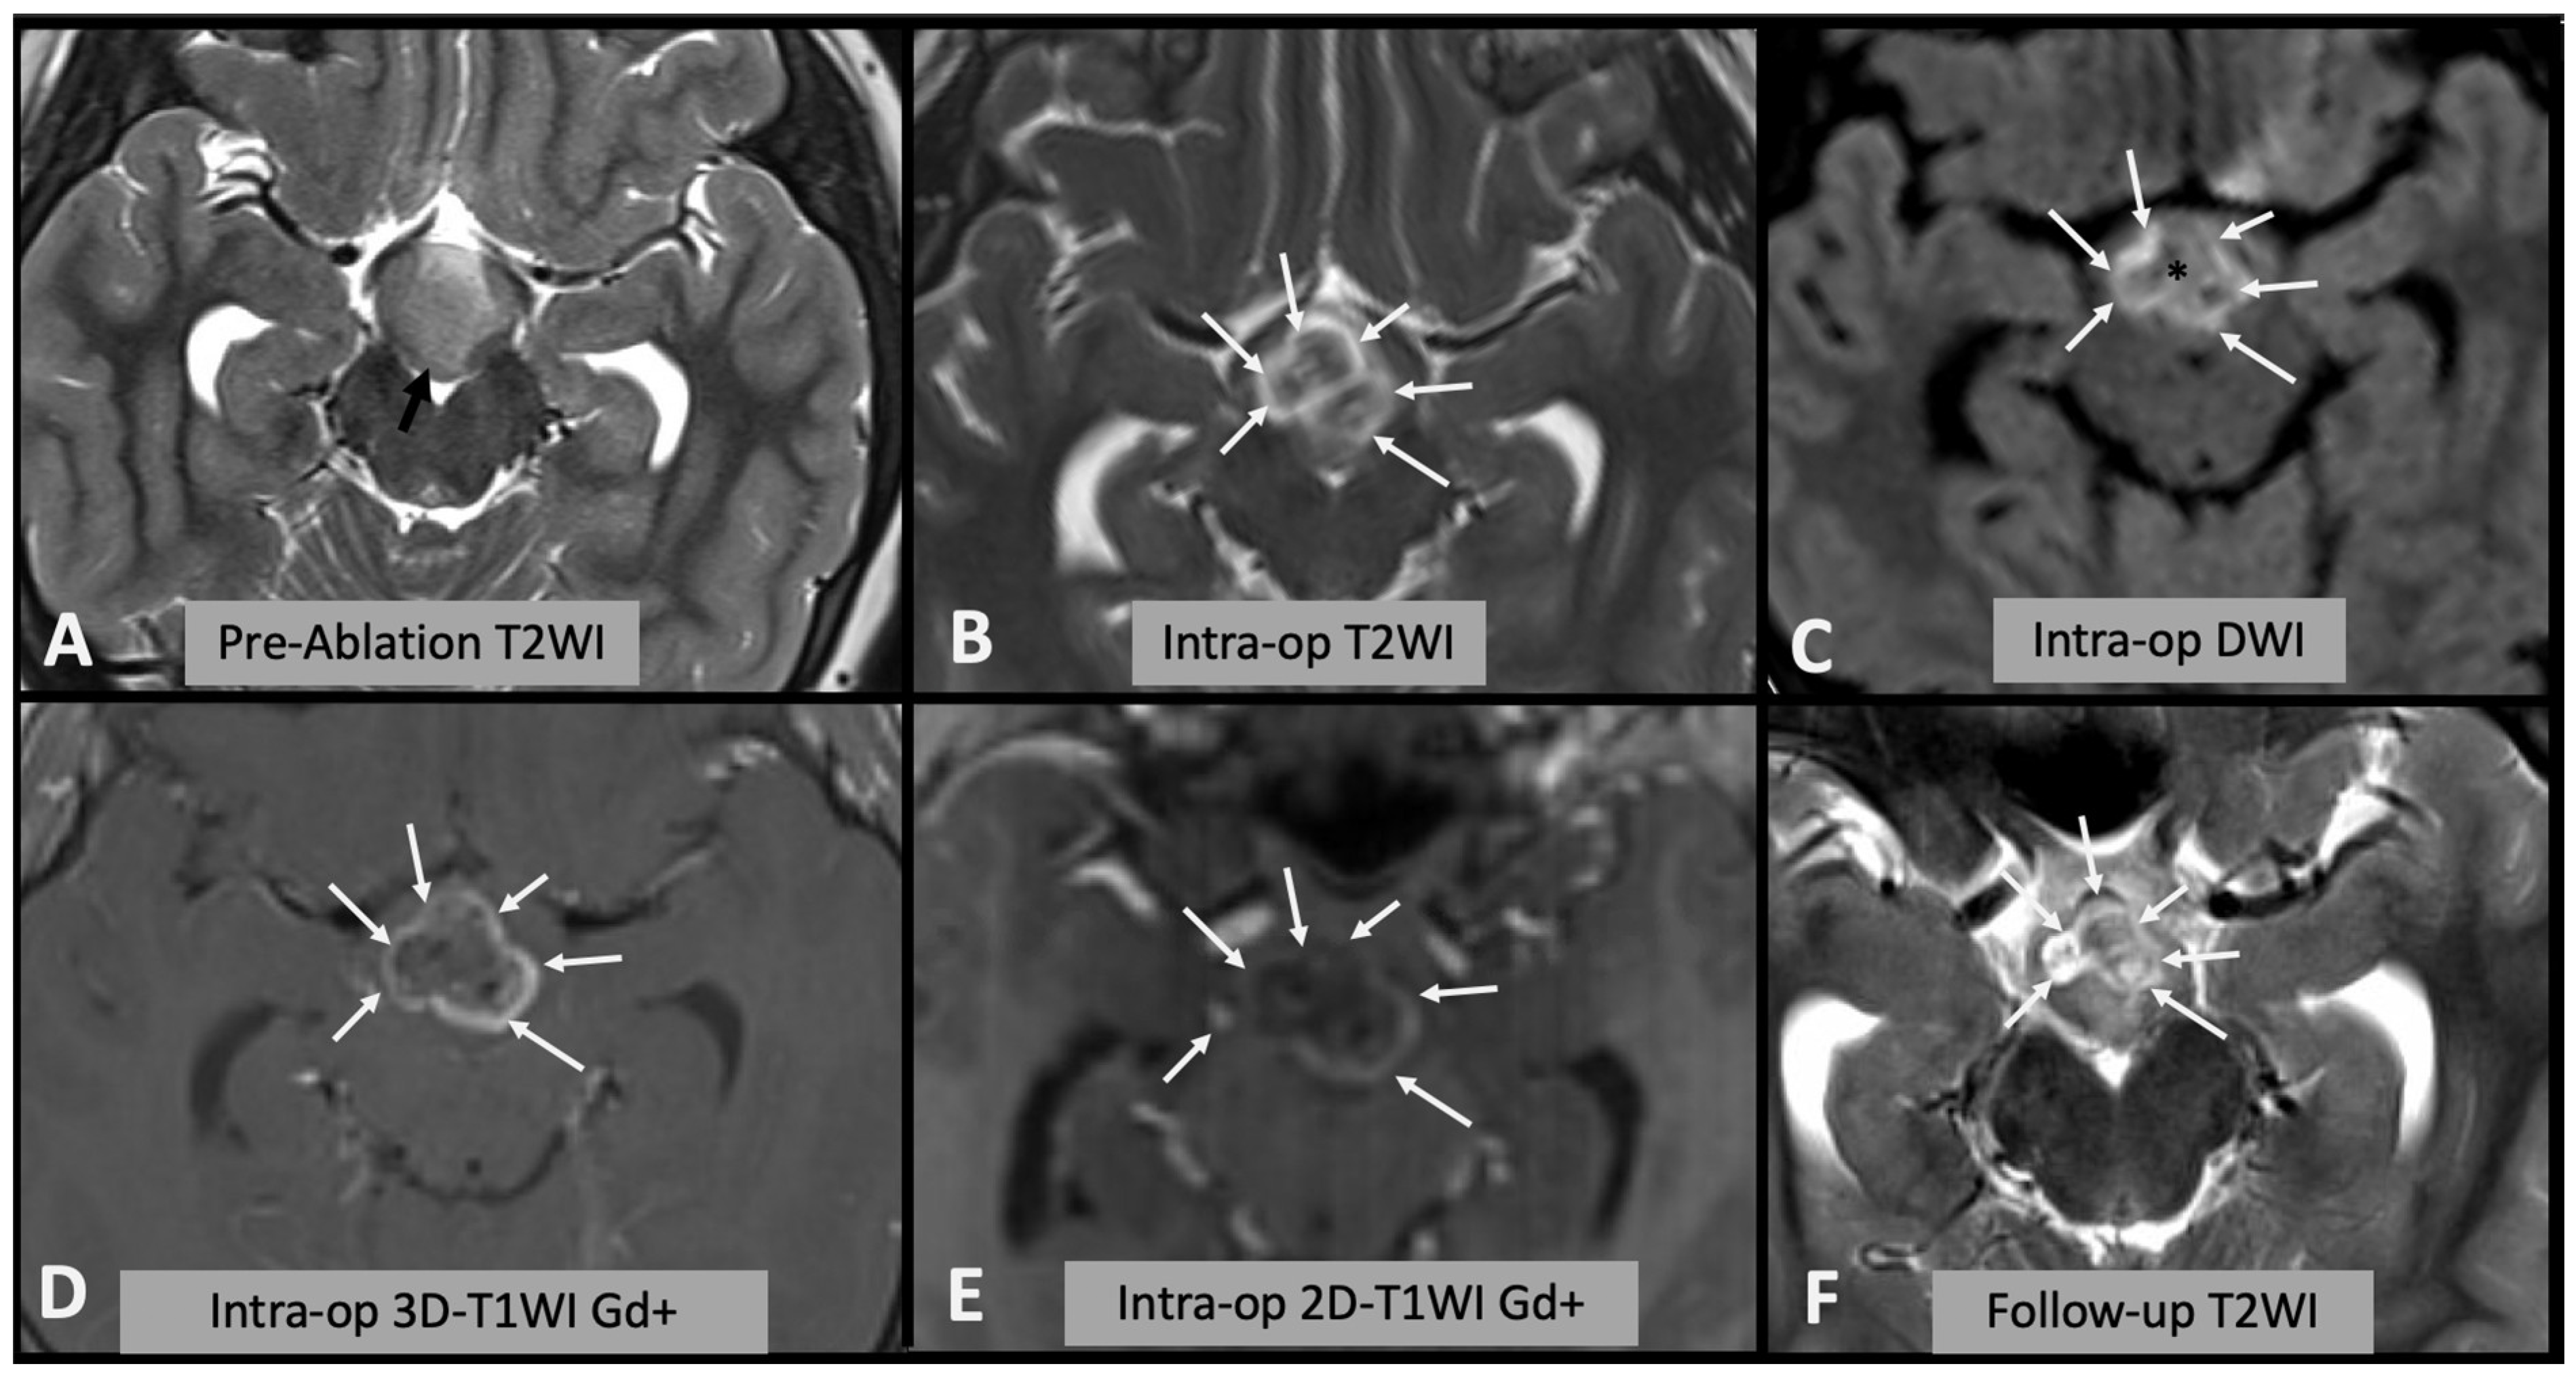

Figure 2. (A) Axial T2WI showing the appearances of the hypothalamic hamartoma before laser ablation (black arrow). (B) Intra-operative axial T2WI immediately before laser ablation, showing the catheter placed in the center of the hamartoma (white arrow). (C) Intra-operative axial T2WI immediately after laser ablation, showing marked T2 hyperintense edema within the hamartoma (white arrows). (D) Intra-operative axial DWI after laser ablation showing hyperintense rim (white arrows) surrounding a hypointense core (asterisk). (E) Post-contrast T1WI sequence showing enhancing rim within the hamartoma (arrows). (F) Follow-up axial T2WI showing the encephalomalacic area of permanent damage; note the central area of T2WI hypointensity corresponding to disconnected hamartomatous tissue.

We assessed the area of signal change on T2WI, DWI (both rim of diffusion restriction and internal hypointense core) and rim of contrast enhancement on T1WI as a percentage of the area of the whole hamartoma and compared the results with the encephalomalacia (fluid area on T2WI on follow-up scan) as a percentage of the whole hamartoma on follow-up (Figure 1). Where residual disconnected tissue was present within the encephalomalacic area, it was considered together with it, as the disconnected tissue is no longer active (Figure 2).

A limitation of this study is that it is based on radiological appearances only. In particular, despite being able to include the disconnected tissue in some of the cases (see Figure 2F), we do not know whether the reversible edema, not evolving in encephalomalacia (i.e., rim of DWI restriction and contrast enhancement), translates to functionally disconnected tissue, hence impacting the procedure’s outcome.